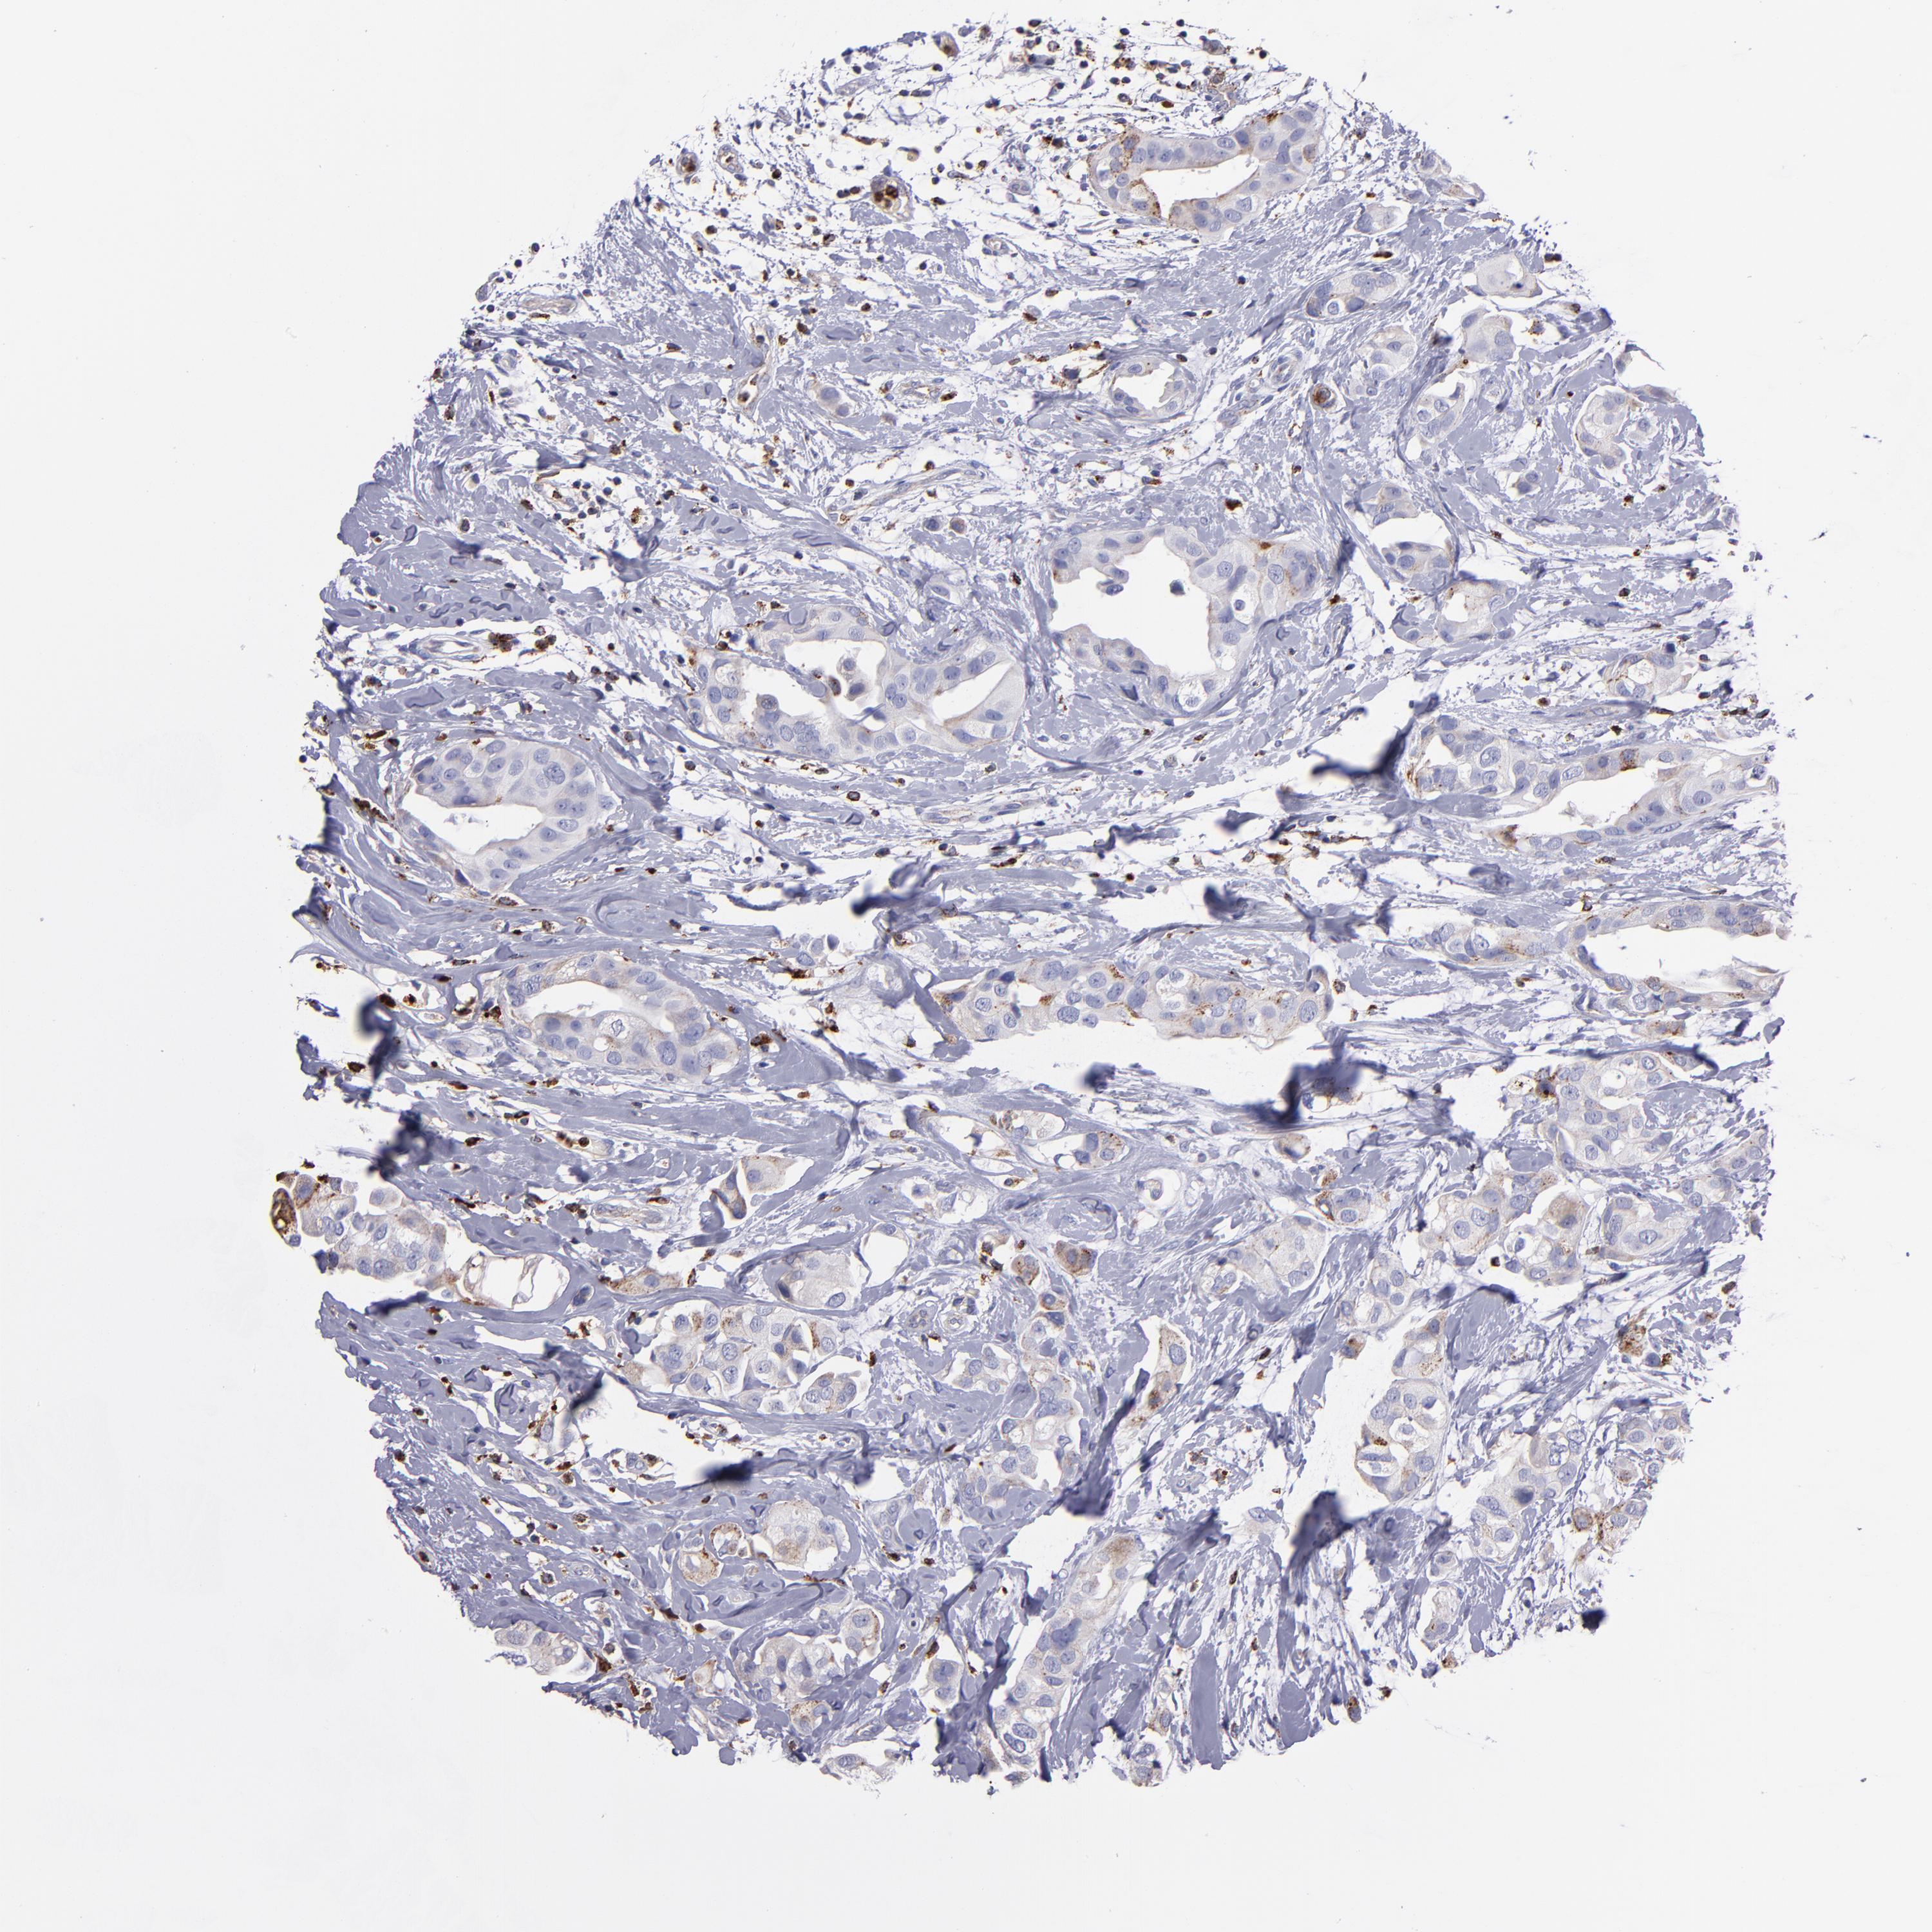

BRCA TCGA BRCA VALIDATION PROTEIN EXPRESSION

ANTIBODIES

AND

VALIDATION